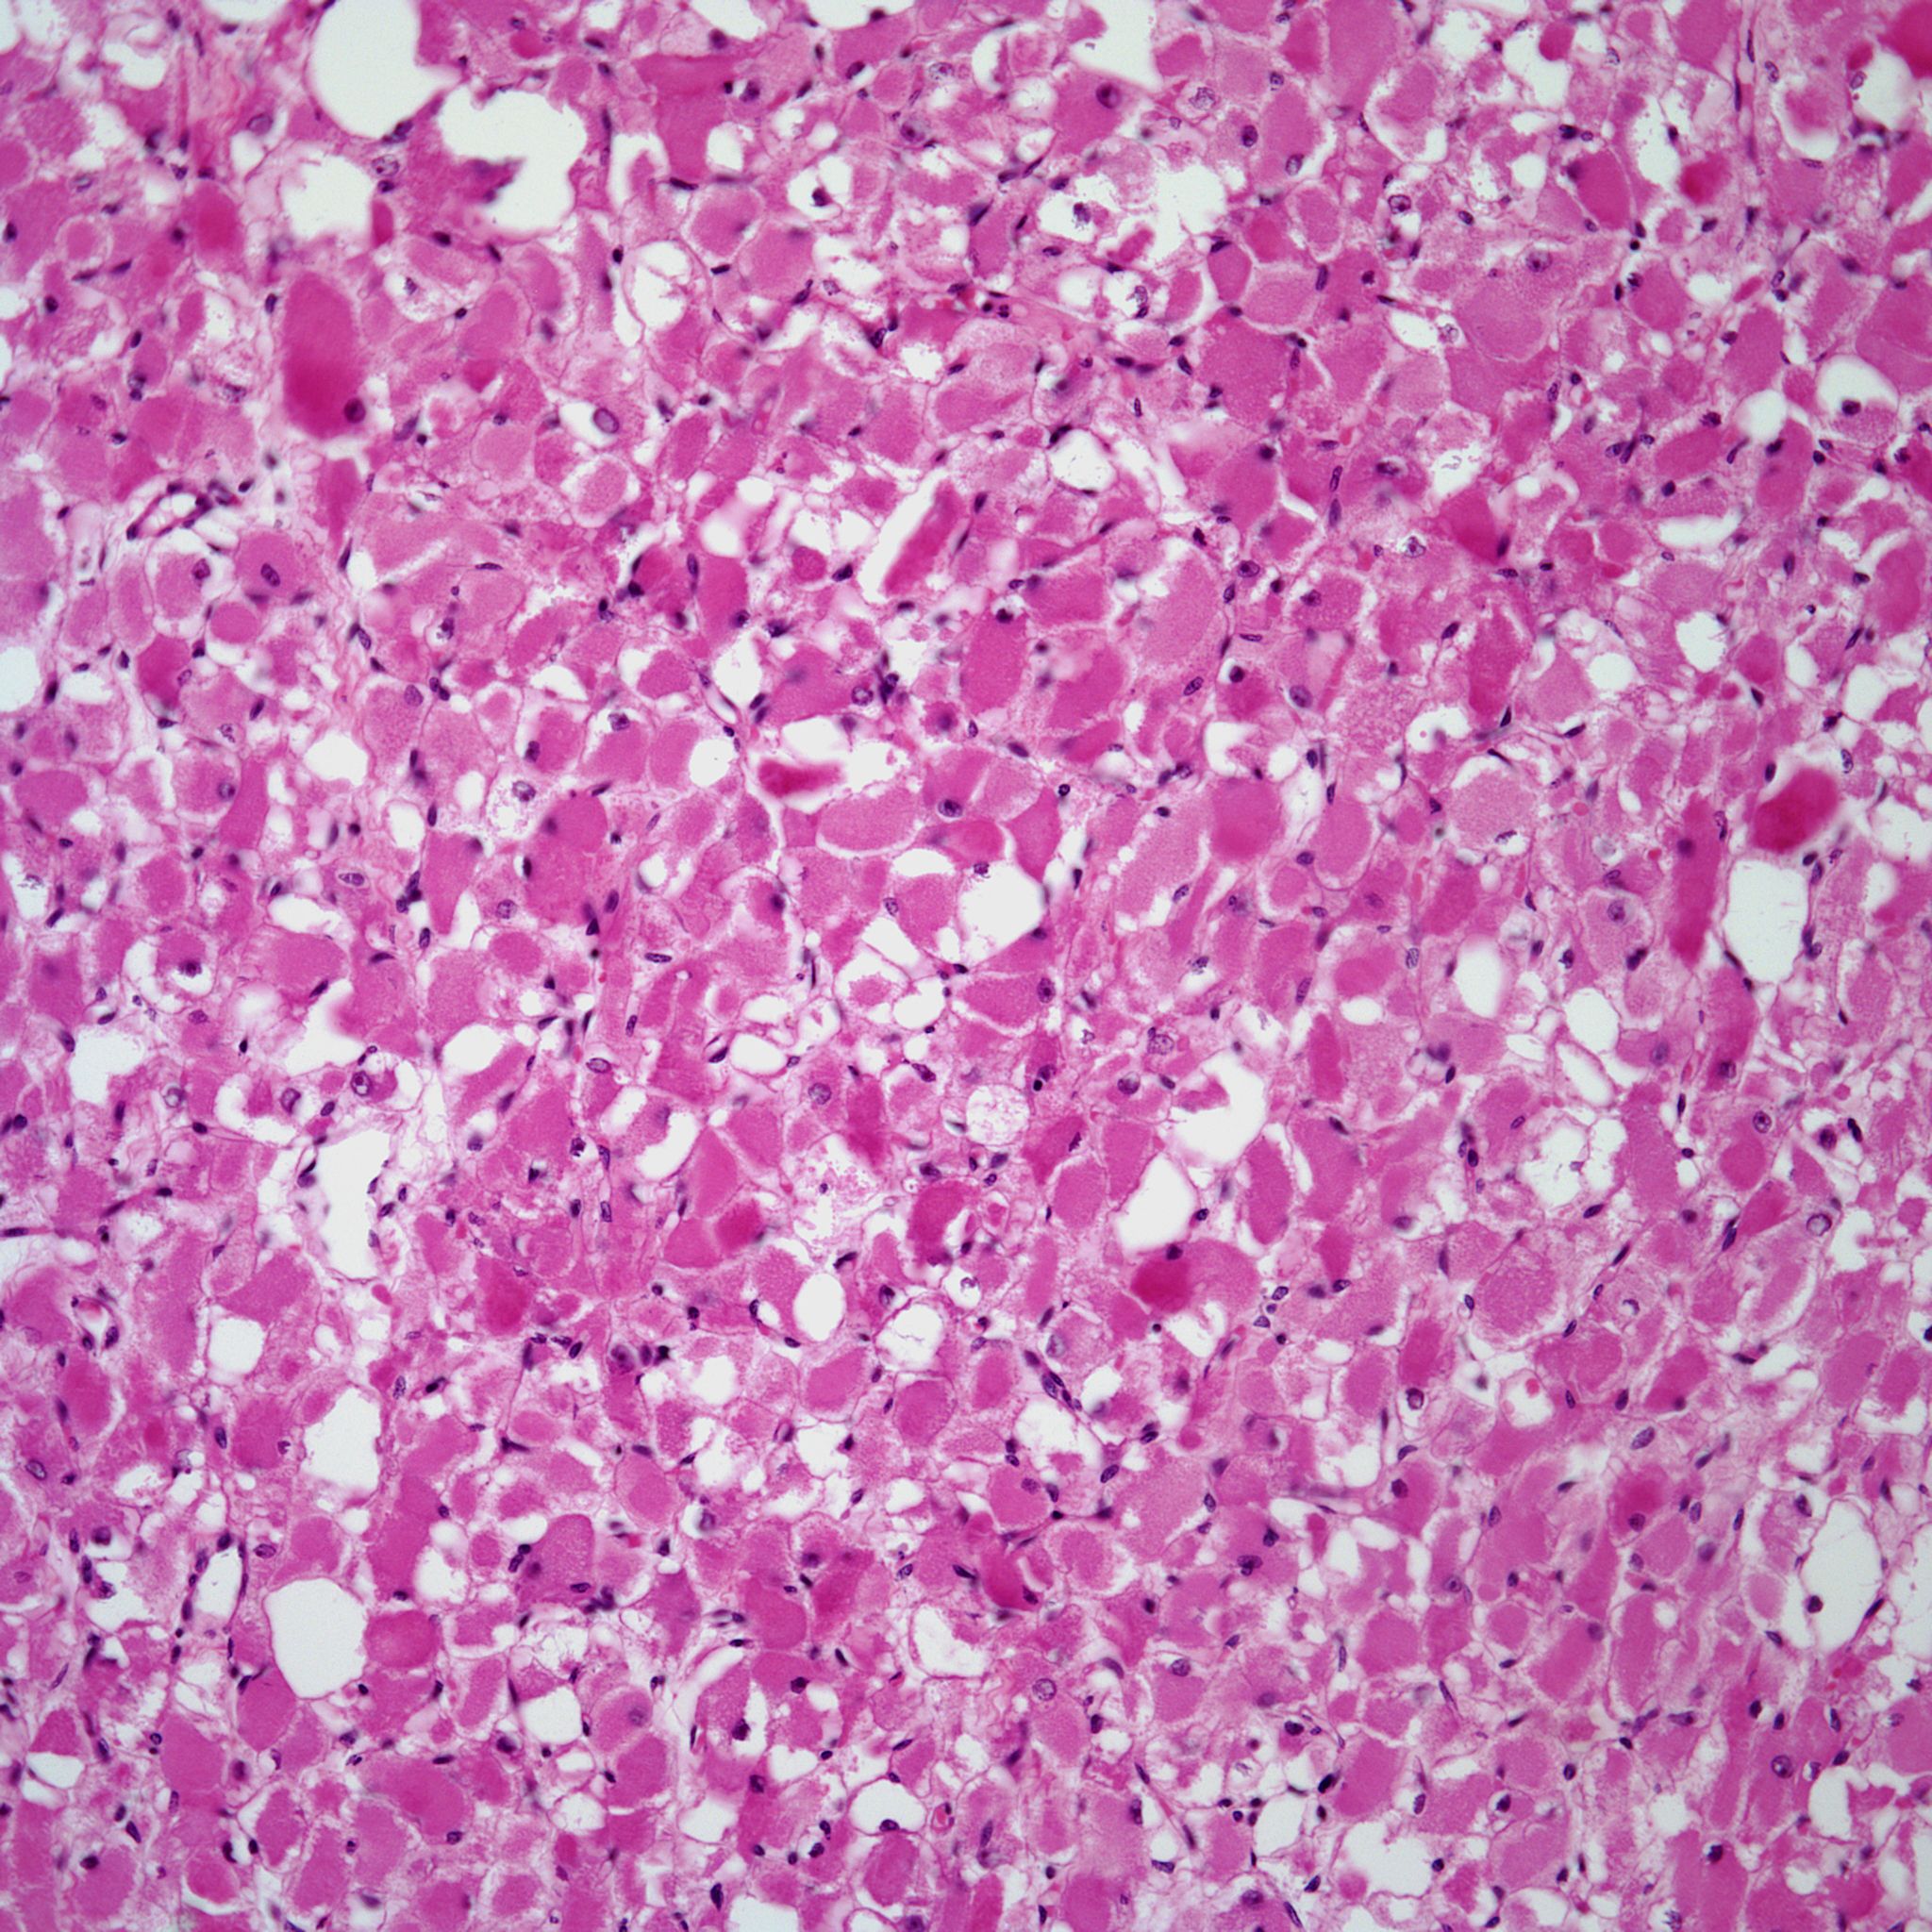

Based on the image shown, what is your diagnosis?